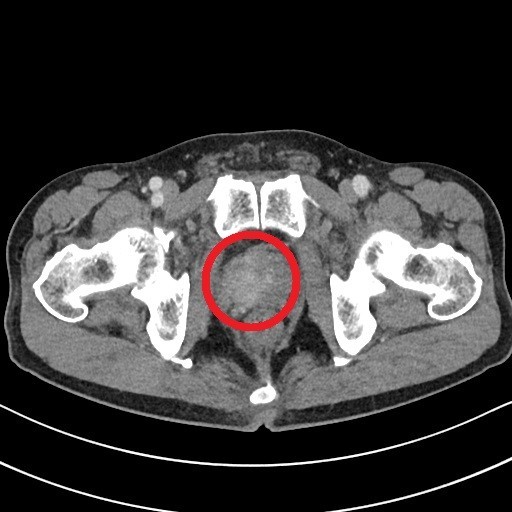

전립선은 방광 바로 아래에 위치하며 요도를 감싸고 있기 때문에, 전립선에 암이 발생하면 주로 소변(배뇨)과 관련된 증상들이 초기부터 나타나는 경우가 많습니다. 다음은 전립선암 환자들이 흔히 겪는 10가지 주요 초기 증상입니다.